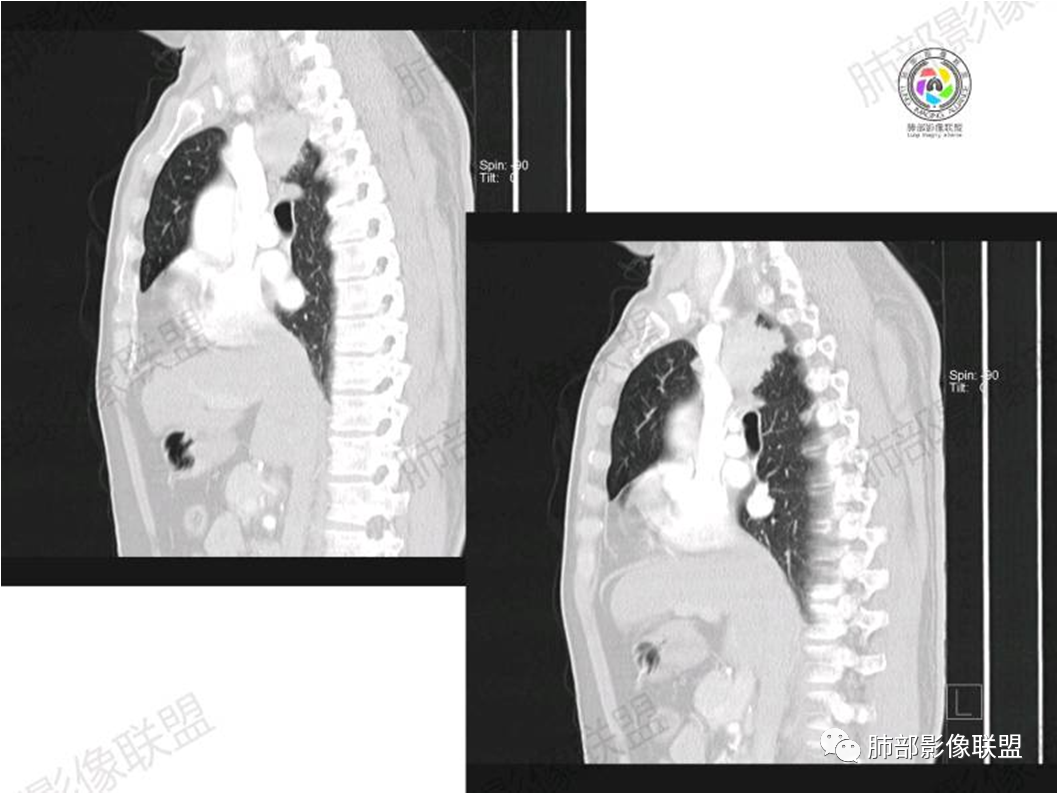

病灶紧贴纵隔胸膜

糊墙,胸膜外未见明显侵犯迹象

病灶整体狭长一些

边缘平直、凹陷为主

支气管外侧带的通畅,片内侧带的似乎中近端狭窄,堵塞

内部肺动脉走形还可以

近端支气管壁弥漫增厚

强化均匀

整体炎性的特点比较明显

不踏实的地方:

边上有些毛糙

恶性待排除

恶性:还是淋巴瘤多见一些。